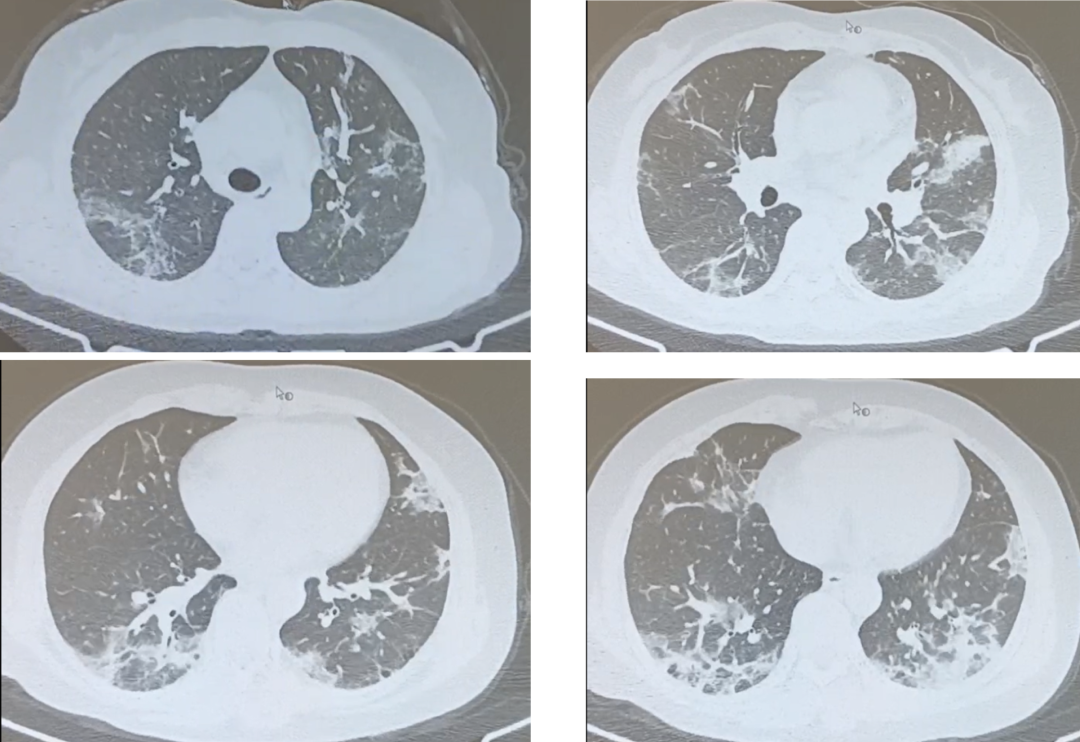

但是,脆弱人群(65岁以上老人,肥胖,合并基础疾病,肿瘤,免疫缺陷等)感染奥密克戎病毒后,可以发展为病毒性肺炎,表现为进行性加重的气短和呼吸困难,呼吸衰竭,甚至休克和多器官功能障碍。图1和图2是最近2周住院的奥密克戎病毒性肺炎肺部CT。

图1:一位48岁男性,有高血压病史10年,肥胖(BMI 31kg/㎡)。这是发病第10天肺部CT,显示双肺弥漫性浸润影和磨玻璃影。呼吸困难进行性加重,鼻导管吸氧5L/min,指测氧饱和度(SpO2)只有93%。

图2:一位49岁女性,有类风湿关节炎14年,卵巢癌术后10年,长期服用泼尼松、雷公藤、甲氨蝶呤。这是发病第13天肺部CT,显示双肺弥漫性斑片影和磨玻璃影。呼吸困难进行性加重,咳嗽咳黄痰,呼吸频率24-25次/分,鼻导管吸氧2L/min,SpO2 96%。